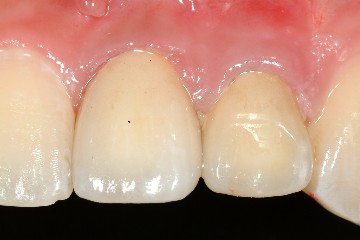

圖十八、十九為技師所完成的全瓷冠成品,氧化鋁全瓷冠有輕微透光性,可將牙齒的金屬釘柱遮光,但色澤與自然牙齒相仿,是牙科2000年後的最新科技發展。圖二十為裝牙齒前的情況,經試戴、調整、及黏著後,過了一週,病患回診所的結果(圖二十一、圖二十二),經過全瓷冠的修復,患者得到滿意的結果,可以再度露出自信且迷人的笑容了。

圖二十一 |